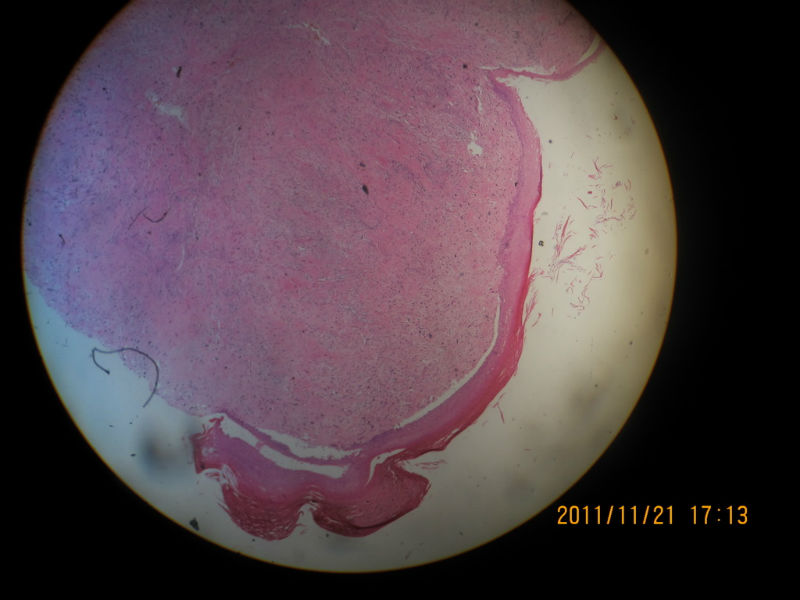

男性,82岁,声带肿物

粘膜下可见怪异的细胞,仍是息肉。

肿瘤大小?肉瘤样癌,恶黑,横纹肌肉瘤,滑膜肉瘤等也需要鉴别

息肉。在声带息肉中容易见到这种怪异细胞,不要过诊断为恶性,让随访观察吧。

感觉很安静,考虑良性。

息肉

结合免疫组化结果最后诊断为恶性纤维组织细胞瘤

诊断恶性纤维组织细胞瘤可以的。那么异型的细胞,息肉不放心。

是恶纤组啊?我还考虑血管源性肿瘤呢。

学习,黏膜下见多形性和异形性明显的细胞弥漫分布,核分裂可见,并见凋亡细胞,首先考虑肉瘤样癌,非典型黄色瘤要考虑,当然组化帮助了我们,临床病史及喉镜检查情况是我们要搜寻的信息。